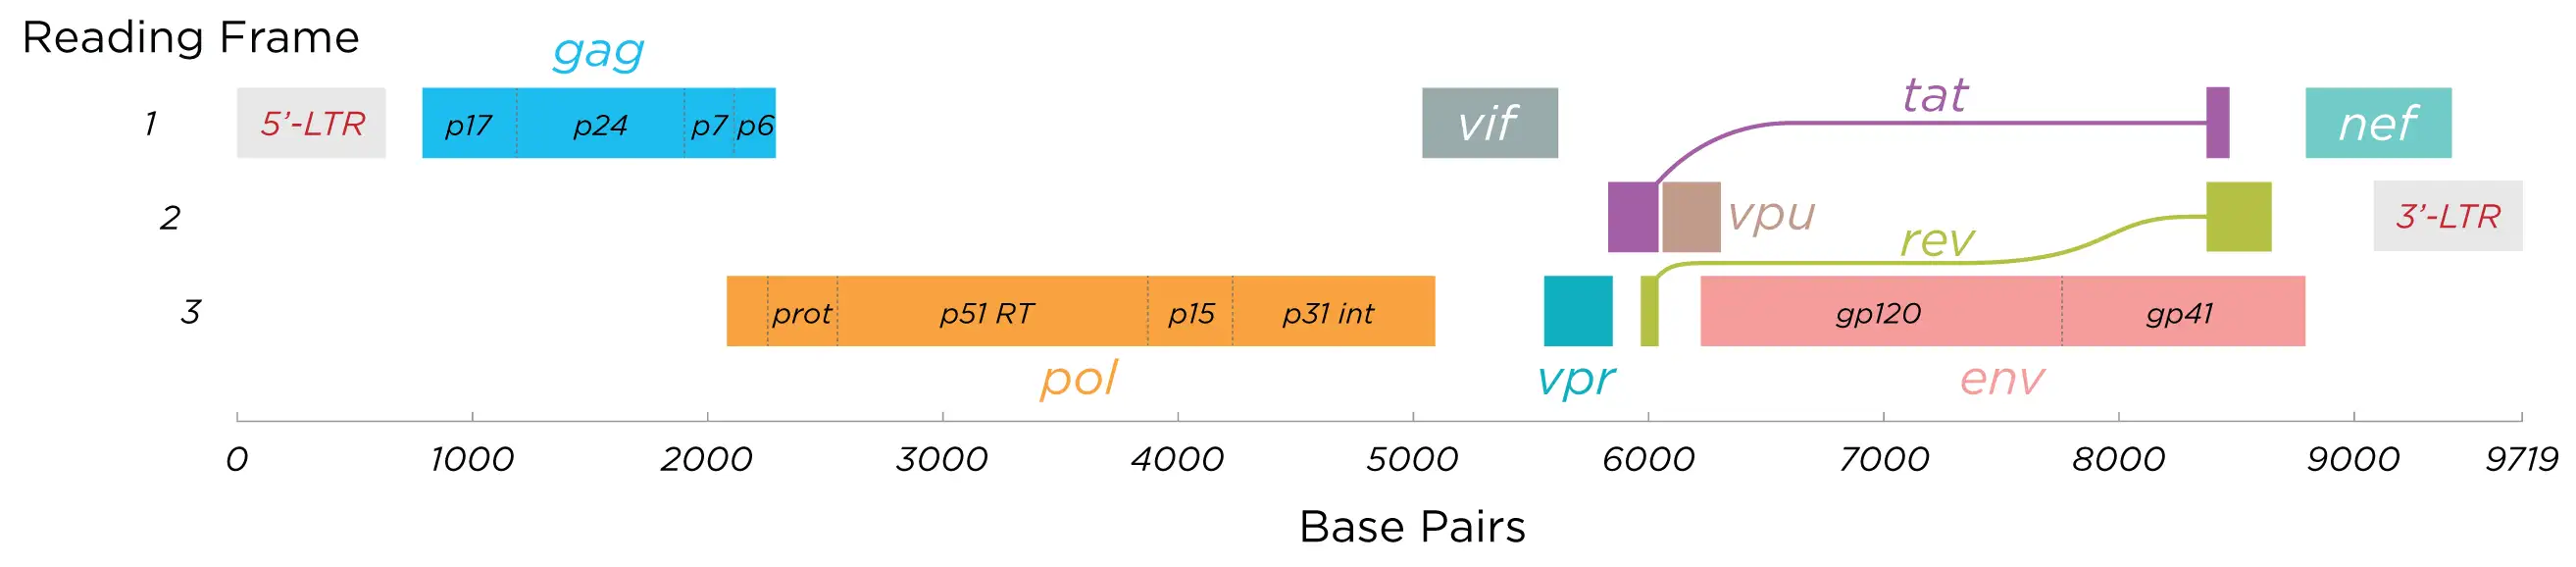

HIV是一种逆转录病毒,这个名称来源于它独特的复制方式。大多数生物的遗传信息流动方向是从DNA到RNA再到蛋白质,但HIV却反其道而行之。它携带的是RNA遗传物质,在侵入人体细胞后,会利用一种叫做逆转录酶的特殊蛋白质,将自己的RNA逆转录成DNA,然后整合到人类细胞的基因组中。这个过程就像是一个黑客将自己的恶意代码植入到操作系统的核心程序里。一旦整合成功,病毒就成为了细胞的一部分,可以潜伏数年而不被察觉。

当HIV进入人体后,其表面的包膜糖蛋白gp120会与T细胞表面的CD4分子结合。这种结合就像是一把钥匙打开了一扇门。随后,病毒会利用细胞表面的另一种受体——CCR5或CXCR4——完成进入细胞的过程。一旦进入细胞内部,病毒就会脱去外衣,释放出自己的遗传物质,开始它的复制周期。

HIV的复制速度惊人地快。一个被感染的细胞每天可以产生数千个新的病毒颗粒。在没有治疗的情况下,人体每天可以产生多达一百亿个新的病毒颗粒。与此同时,HIV的逆转录酶极其容易出错,平均每次复制都会引入新的突变。这种高突变率使得病毒能够快速进化,逃避人体的免疫反应和药物的作用。

一九九五年,华裔科学家何大一和他的团队提出了鸡尾酒疗法的概念。这种方法的核心是同时使用三种或更多种不同机制的药物来攻击病毒。就像是用多把锁来关住一扇门,即使病毒破解了一把锁,其他锁仍然可以将它困住。临床实验表明,鸡尾酒疗法可以将患者血液中的病毒载量降低到检测不到的水平,同时显著提高CD4细胞计数。

疫苗的开发仍然是一个遥不可及的目标。HIV的高突变率和免疫逃逸能力使得传统疫苗策略几乎无效。几十年来,科学家们尝试了各种方法——灭活病毒、重组蛋白、病毒载体、DNA疫苗、mRNA疫苗——但没有一种能够在临床实验中展现出足够的保护效果。